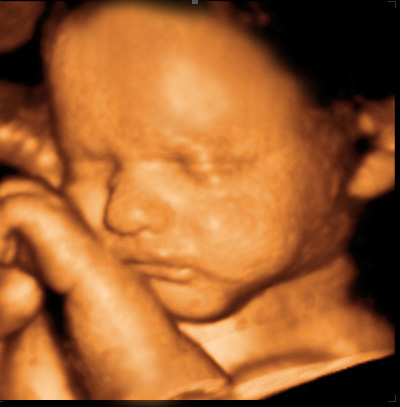

4D 초음파는 3D 입체 영상에 실시간 움직임을 더해 보여주는 방식입니다. 즉, 정지된 입체 사진이 아니라 태아의 표정이나 손발 움직임, 자세 변화를 보다 생생하게 확인할 수 있도록 도와주는 초음파입니다.

예비 부모 입장에서는 태아의 모습을 조금 더 구체적으로 확인할 수 있어 정서적인 안심에 도움이 될 수 있고, 의료진의 설명을 시각적으로 이해하는 데도 도움이 될 수 있습니다.

반면 4D 초음파는 태아의 얼굴, 자세, 움직임 등을 보다 입체적으로 보여주는 데 강점이 있습니다. 따라서 의학적 판단의 기본은 일반 초음파와 정밀 평가가 중심이고, 4D 초음파는 이해를 돕거나 추가적으로 시각화가 필요한 경우 활용될 수 있다고 보는 것이 더 자연스럽습니다.